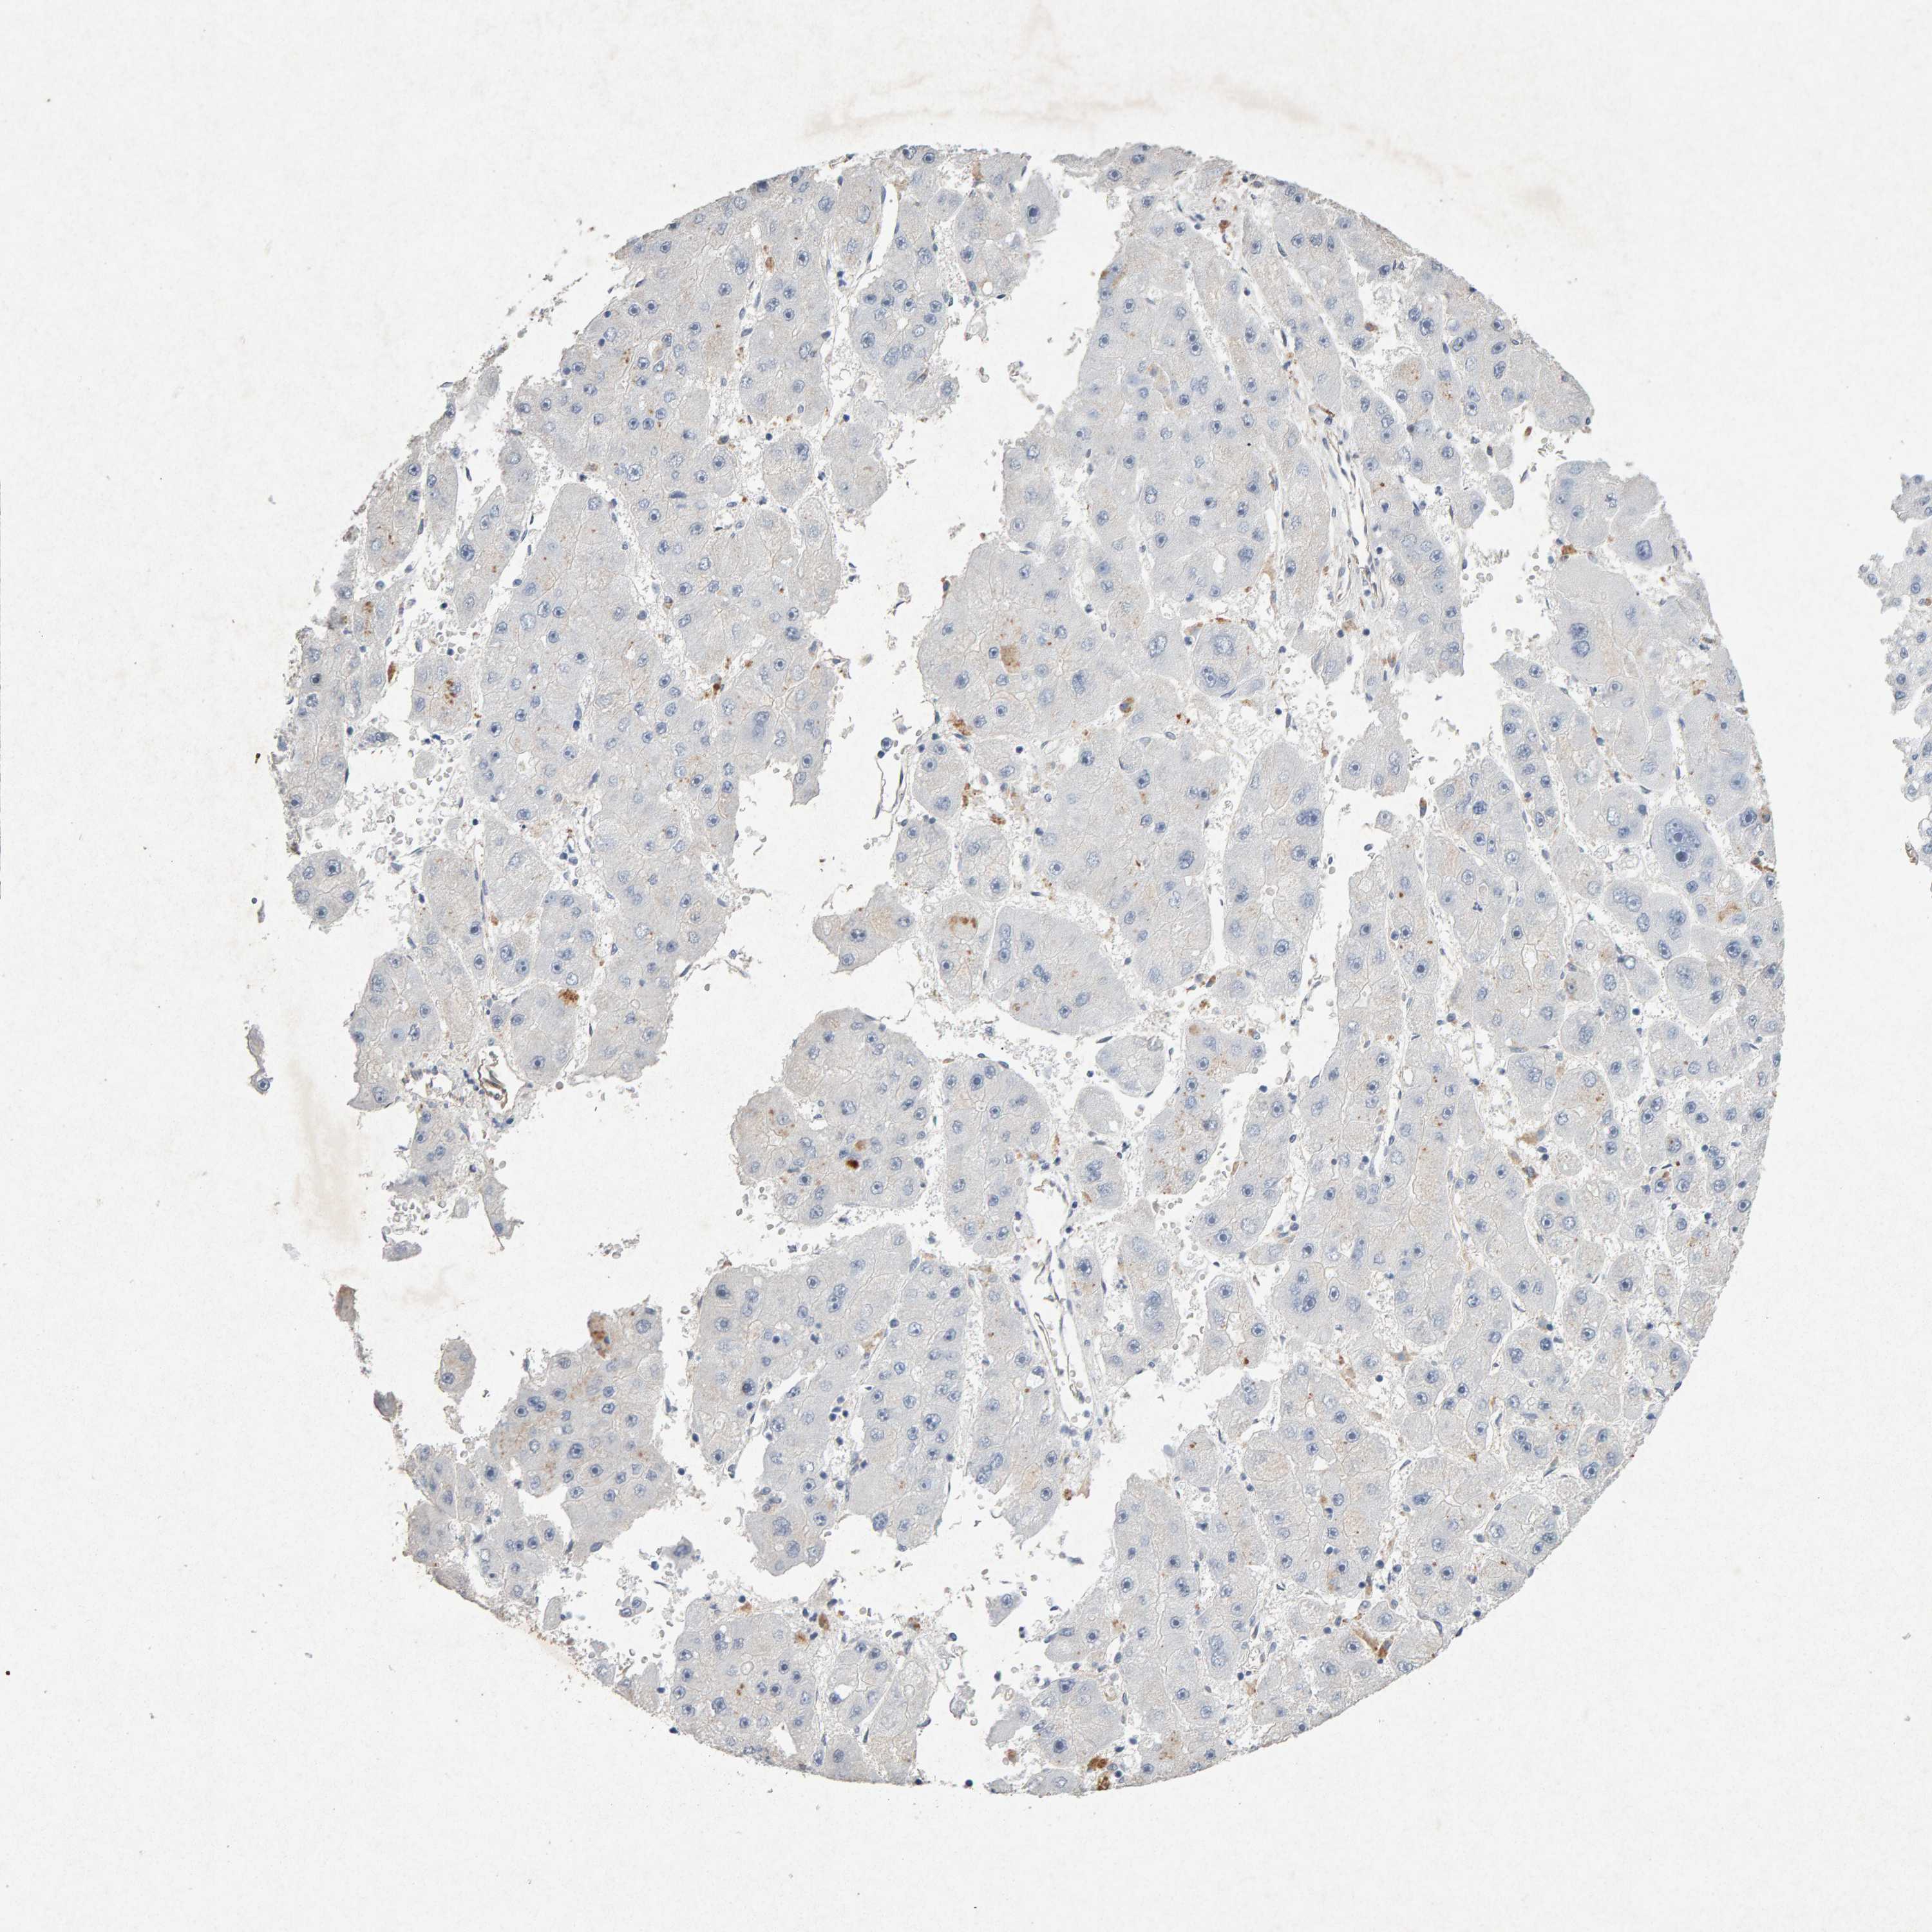

LIVER CANCER - Protein expressioni

A mouse-over function shows sample information and annotation data. Click on an image to view it in a full screen mode. Samples can be filtered based on level of antibody staining by selecting one or several of the following categories: high, medium, low and not detected. The assay and annotation is described here.

Note that samples used for immunohistochemistry by the Human Protein Atlas do not correspond to samples in the TCGA dataset.

Antibody stainingi

Antibody staining in the annotated cell types in the current human tissue is reported as not detected, low, medium, or high, based on conventional immunohistochemistry profiling in selected tissues. This score is based on the combination of the staining intensity and fraction of stained cells.

Each image is clickable and will lead to virtual microscopy that enables deeper exploration of all samples and also displays staining intensity scores, fraction scores and subcellular localization as well as patient and tissue information for each sample.

Antibody CAB022442

Antibody CAB022443

Staining

Cholangiocarcinoma

Carcinoma, Hepatocellular, NOS